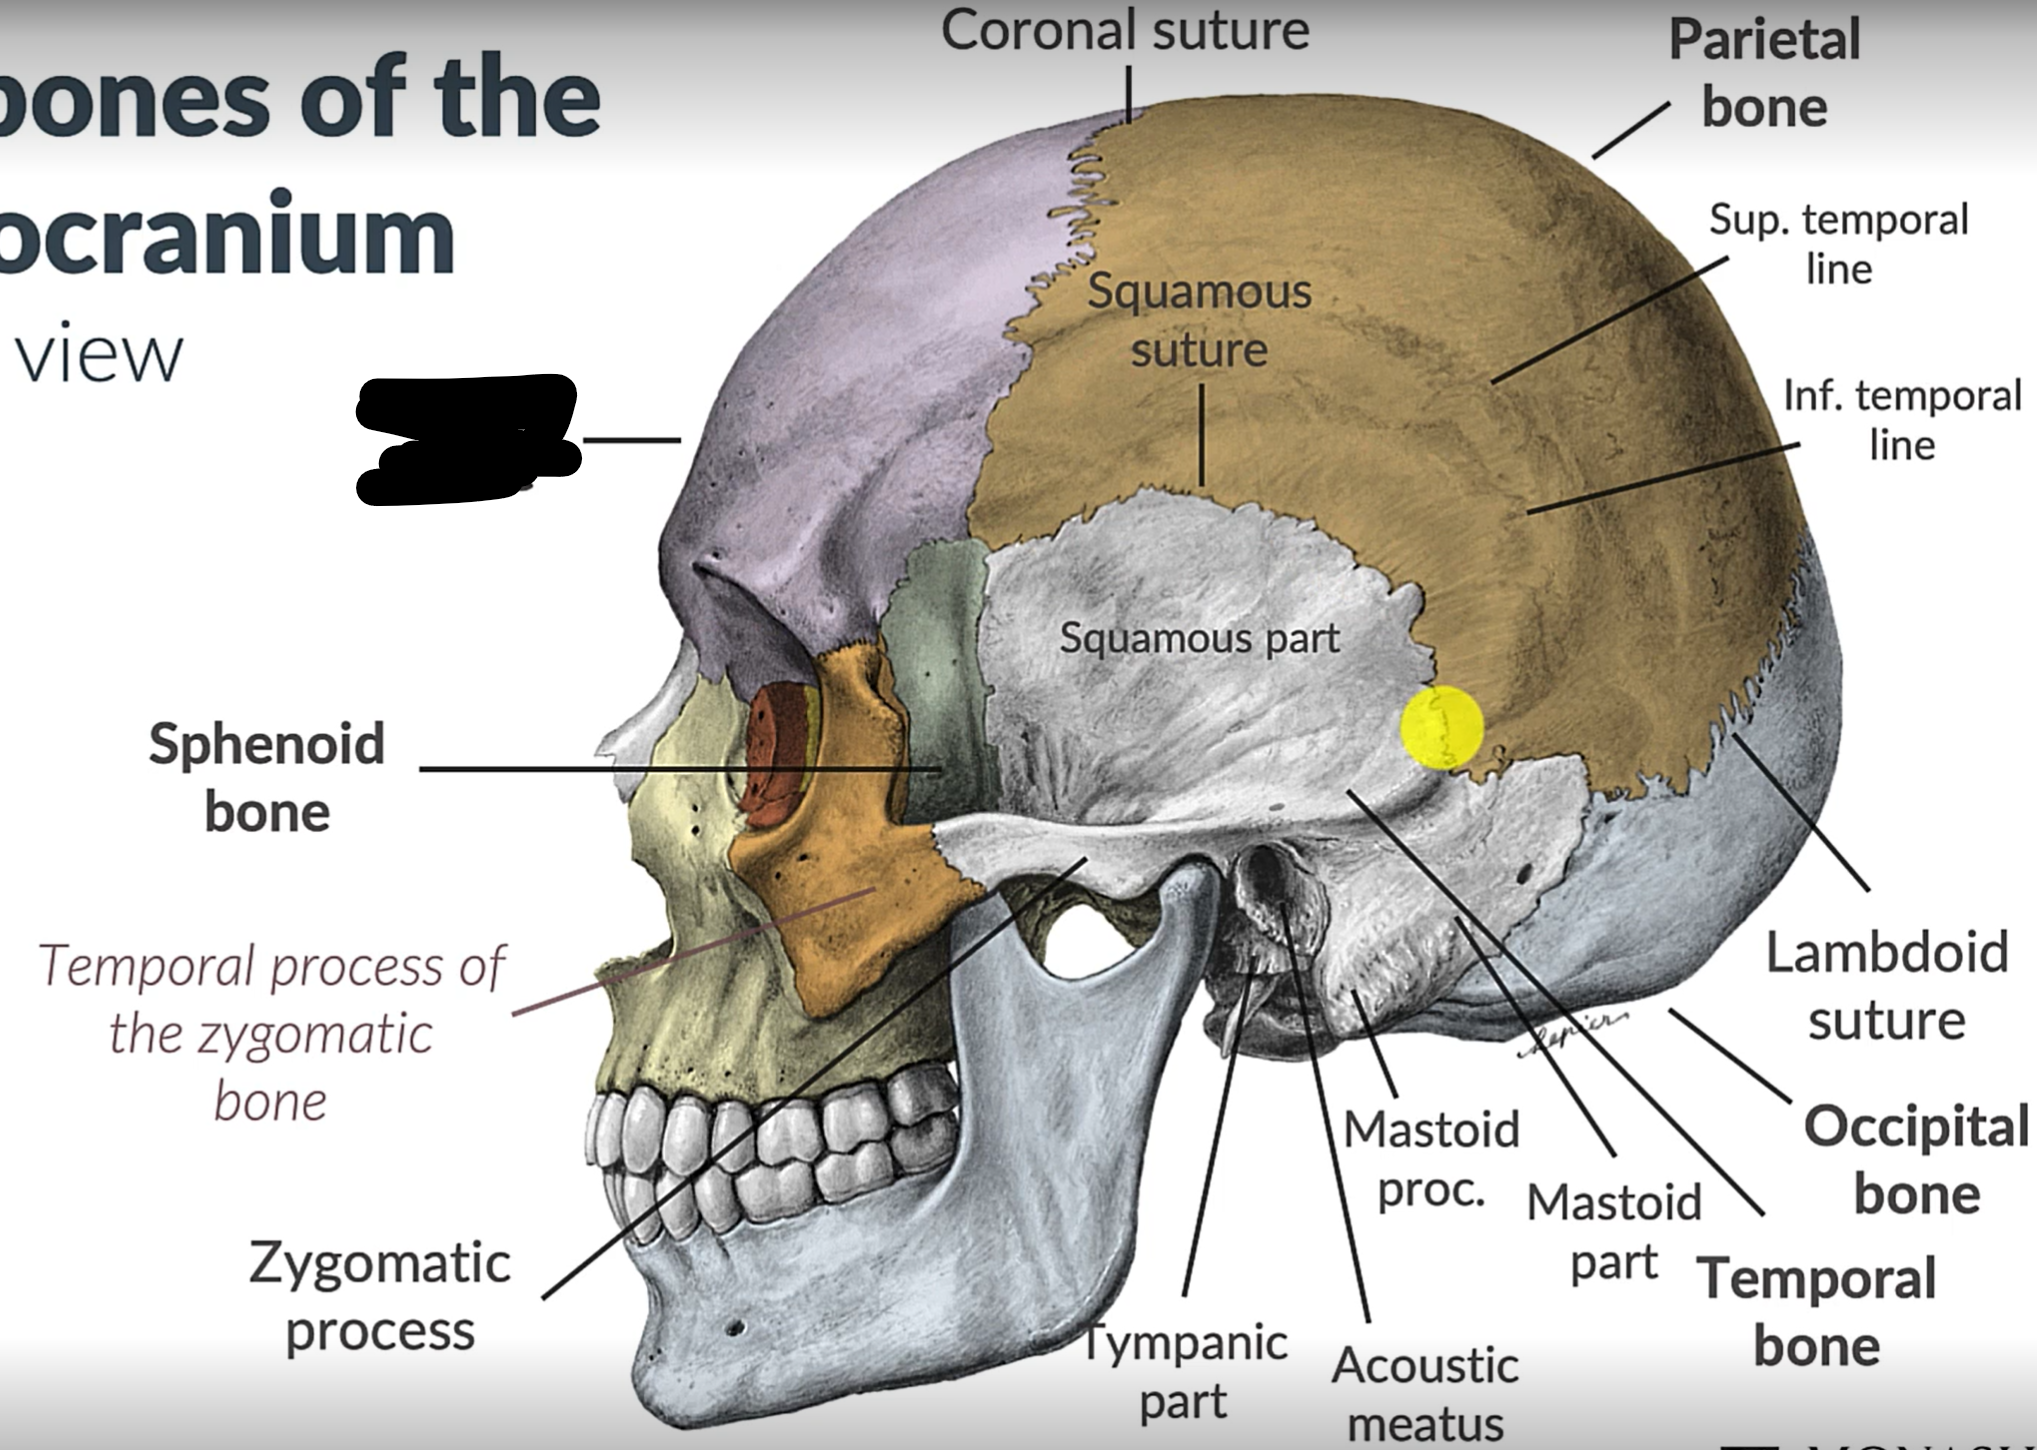

Frontal bone

Coronal suture

Parietal lobe

Squamous suture

Lambdoid suture

Occipital bone

Temporal bone

Zygomatic process

Sphenoid bone

What is the pterion?

The point where the frontal, parietal, sphenoid and temporal bones meet.